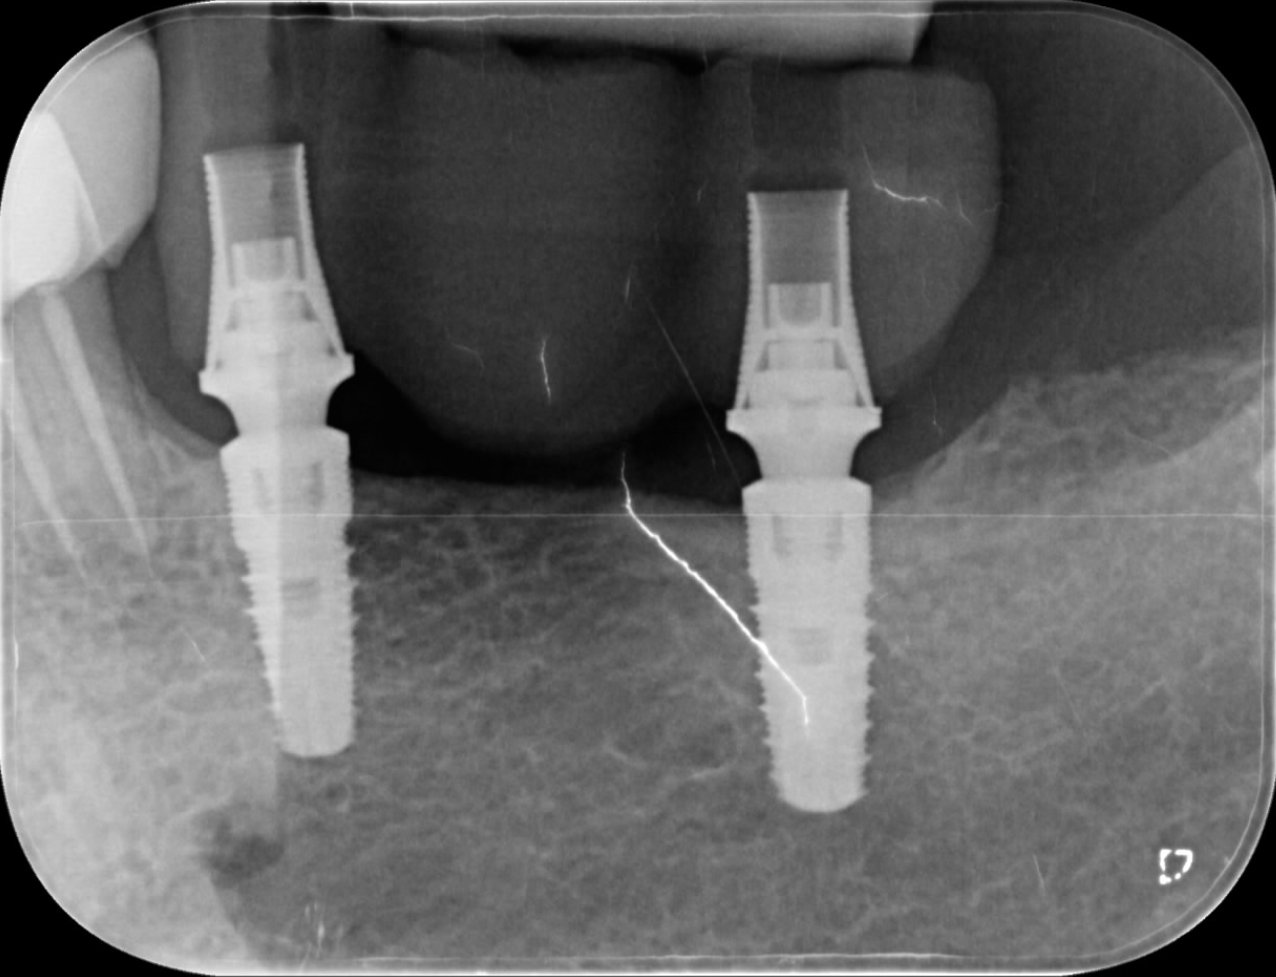

A 72-year-old patient in good general health presented with partial edentulism in the maxillary posterior region. The main goal was to achieve a rapid fixed prosthetic rehabilitation. After clinical and radiographic (2D and 3D) analysis, it was decided to proceed with a screw-retained bridge on implants, using multi-unit abutment connections to compensate for angulation and z-axis discrepancies. After guided surgery to place two internal hexagonal/conical connection implants, osseointegration time was allowed before prosthetic loading. The patient was informed that the entire prosthetic treatment would be completed on one day, since there would be no need for an external laboratory.

Intra-oral scanning After postoperative healing of the implants, multi-unit abutments and ProCam scan bodies were placed over the implants, and data was acquired with the Medit i700 wireless intra-oral scanner (Figs. 2a & b). The use of the intra-oral scanner allowed us to avoid physical impressions, thereby reducing patient discomfort. It also allowed for the capture of a detailed and accurate digital representation of the implant connections and enabled real-time evaluation of the scan quality.

The use of intra-oral scanners to capture impressions has demonstrated high accuracy compared with conventional techniques.1, 2 The importance of ensuring a precise intra-oral scan is often under-estimated, and accurate intra-oral data capture is the true starting point for a successful restoration. Accurate transfer of the implant position is essential for achieving a perfect match between the digital design and clinical reality. Having an optimised geometry and being made of a highly readable scanning material, the ProCam scan bodies allowed the position of the implants and the profile of the peri-implant tissue to be captured with extreme fidelity (Fig. 3).